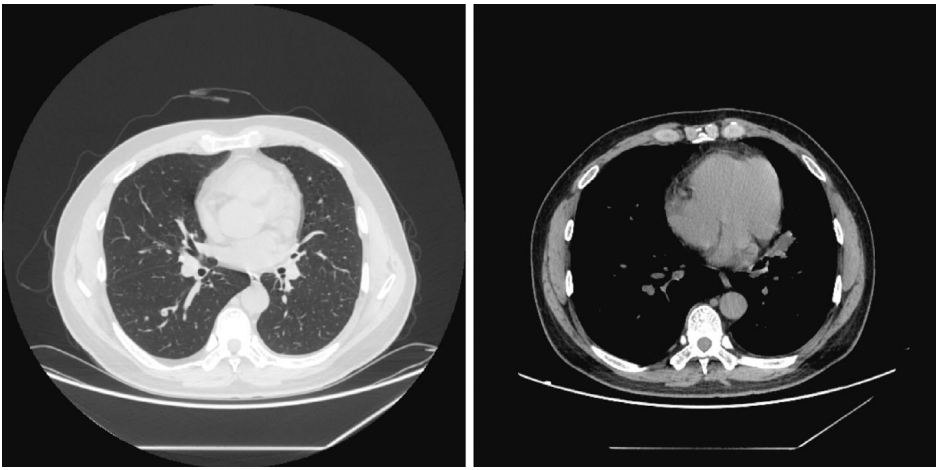

检查了肿瘤标记物,发现血清癌胚抗原(CEA)和多糖抗原19-9(CA19-9)水平急剧下降。患者继续接受派姆单抗联合培美曲塞和卡铂治疗。第三个疗程后,胸部CT扫描显示弥漫性肺小结节完全消退,左上叶病变稳定(图1(c))。在一线治疗期间,患者无进展生存期(PFS)为9个月,疾病得到控制。2021年3月,发现左上肺的病变和肿瘤标记物增加(图1(d))。随后进行经支气管肺活检,确认肿瘤进展。肿瘤组织的NGS显示与第一次活检相同的EGFRex20ins突变。此后,从2021年3月开始患者每3周接受一次派姆单抗加多西他赛和贝伐单抗治疗 ,疾病保持稳定(图2)。该患者定期随访至2021年7月。

图2. 胸部计算机断层扫描(CT)显示,接受派姆单抗、多西紫杉醇和贝伐单抗治疗后,左肺和双侧肺结节病变稳定